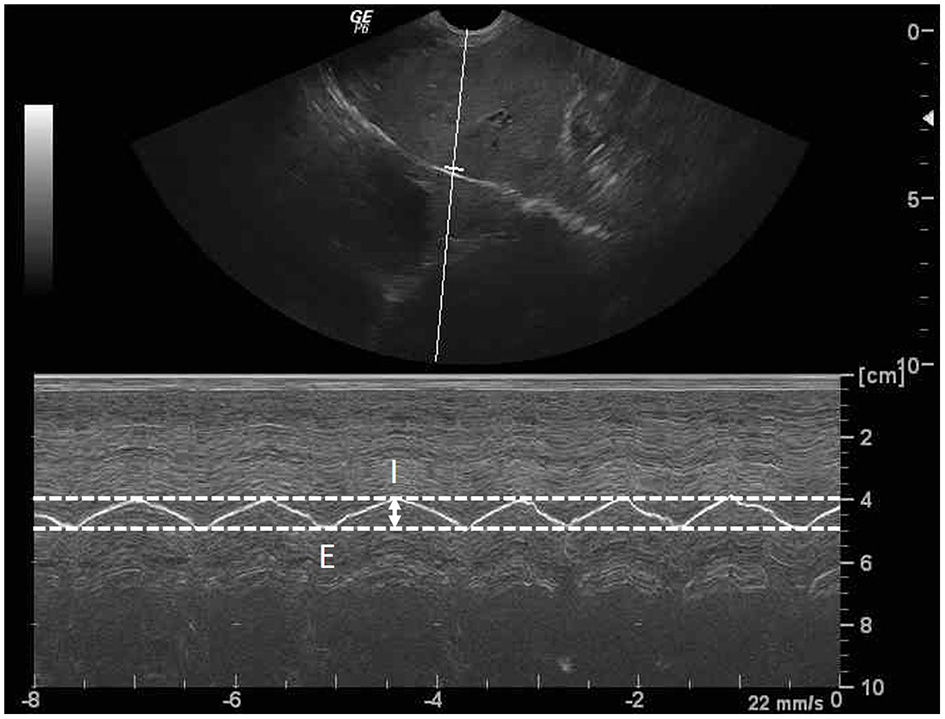

Figure 3

Sagittal ultrasonographic image of the diaphragm with motion (M)-mode display showed the measurement method for diaphragmatic excursion (DE; arrow). DE is the different distance of diaphragm between the peak inspiration (I) and the peak expiration (E).